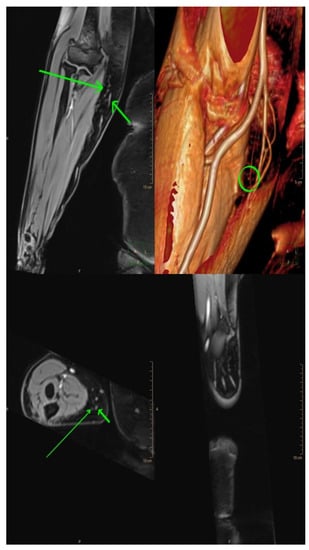

Figure 3.

Magnetic resonance lymphangiography provides anatomic delineation and 3D reconstruction images of lymphatics and adjacent veins. Long arrows = lymphatic channels; short arrows = vein; and circle = the crossing of both (the possible place of incision).